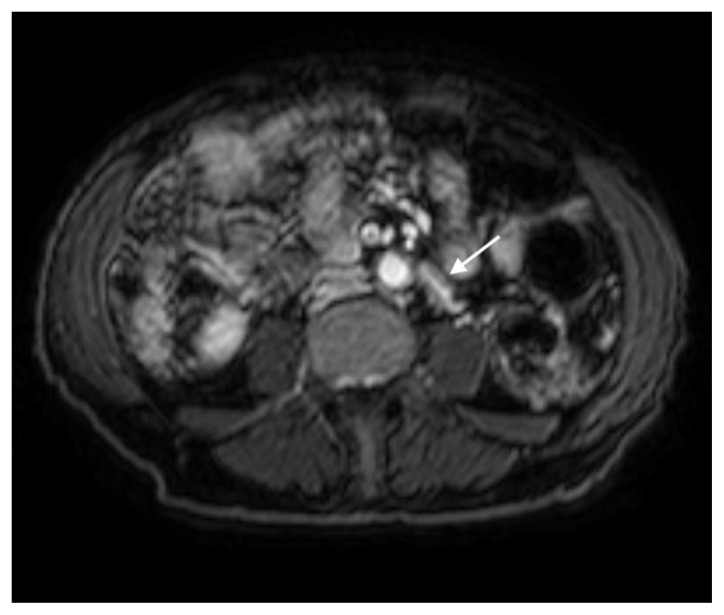

Figure 11.

78 year-old male with IgG4-related autoimmune disease.

Findings: DWI MRI demonstrates hyperintense soft tissue surrounding the IMA (arrow).

Technique: Axial DWI-weighted (1.5T, TR 1372, TE 62.5, slice spacing 6.6)

The MRI revealed soft tissue encased the proximal common bile duct (CBD) and biliary hilum, resulting in a 4cm-long stricture, with increased upstream intrahepatic biliary dilatation (Figures 5, 6). The hepatic parenchyma demonstrated diffuse heterogeneous enhancement, without a focal mass or pseudotumor, consistent with inflammatory changes. The pancreas demonstrated parenchymal T2 hyperintensity and T1 hypointensity with diffuse enhancement, including an enhancing peripheral soft tissue rind, again consistent with autoimmune pancreatitis (Figure 7). The kidneys also demonstrated multifocal regions of abnormal enhancement and restricted diffusion (Figure 9, 10). Persistent enhancing soft tissue surrounding the SMA and IMA was again noted (Figure 11, 12).